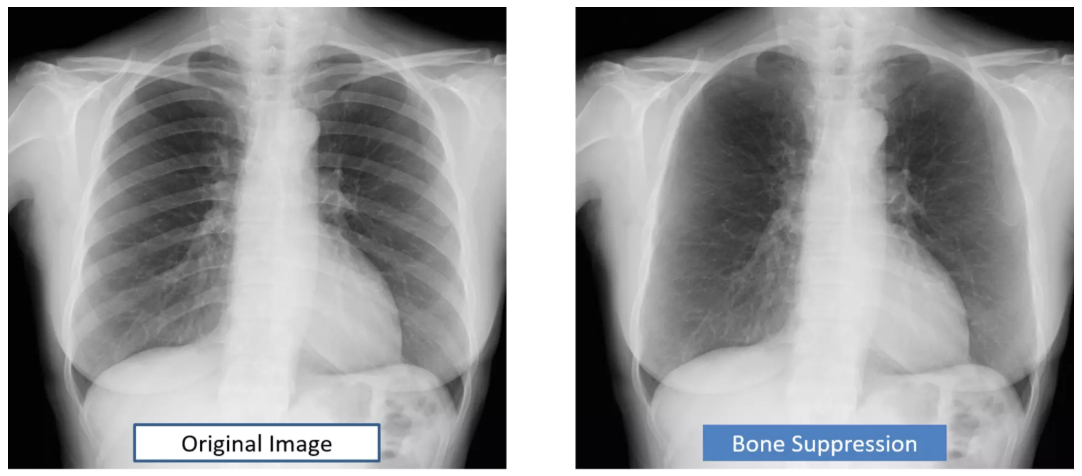

AeroDR NS

The next standard for digital upgrades